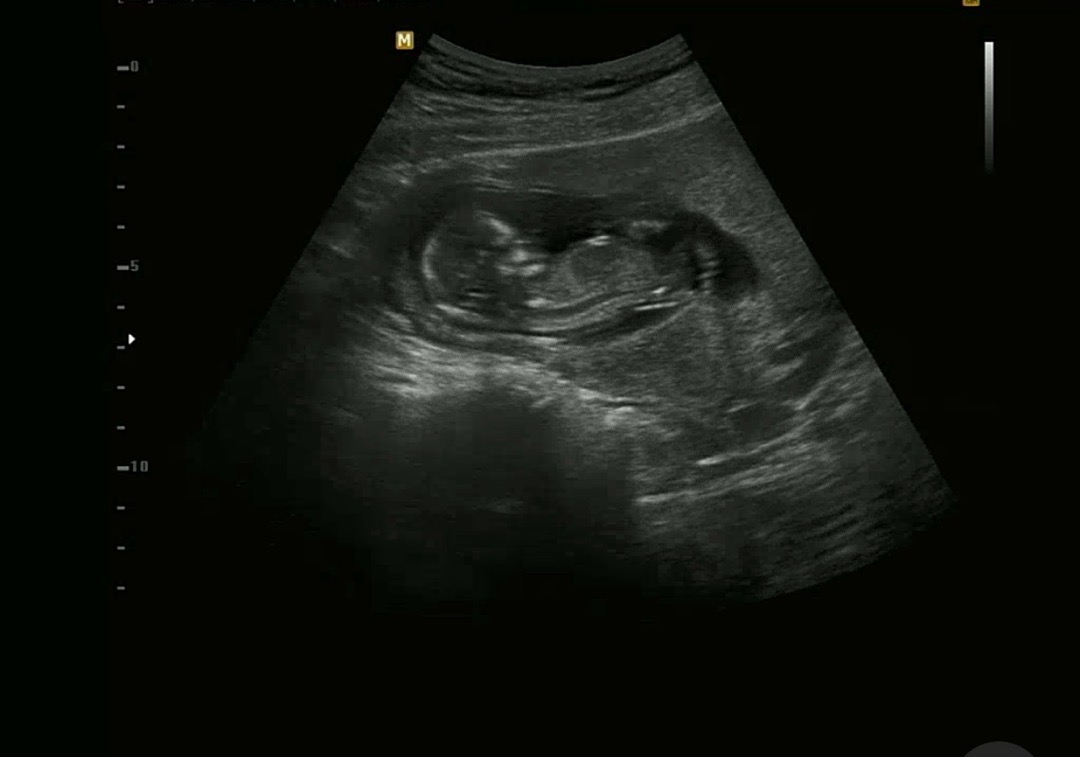

아기가 낑겨있는것 같나요?😭

13주고 처음으로 배초음파로 봤어요 초음파가 각도에따라 다르게 보인다고 하던데 선생님은 아무말씀 안하셨는데, 신랑이 아기가 낑겨있는거 같다며ㅋㅋㅋ 그말들으니 낑겨있는거 같기도 하고... 입덧도 심한데 원래 물을 거의 안마시긴해요ㅠㅠ 루이보스티라도 열심히 마시면 괜찮겠죠...?

초음파 자체가 2D로 보여주는 거기 때문에 3D로 봤을 때랑은 차이가 많이나요 대부분은 저렇게 보이더라구요 아마 의사쌤이 별말안하셨다면 이상없는 게 맞습니다ㅎㅎ